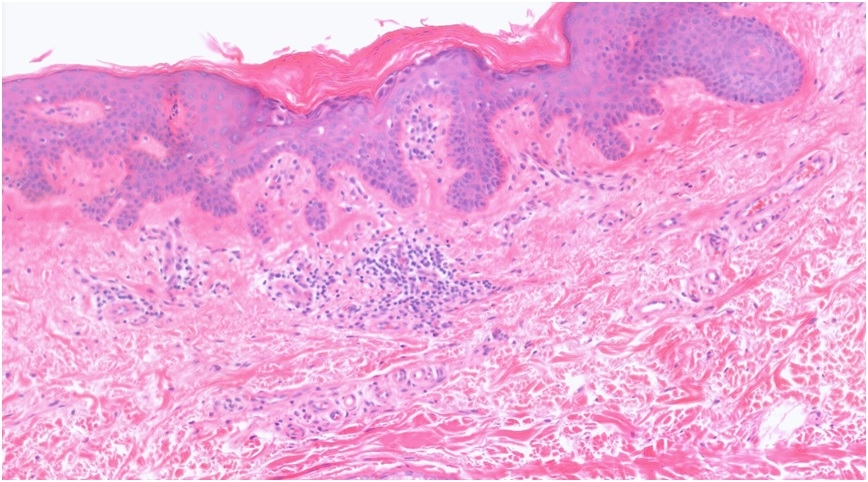

A: 74M, Mid back Biopsy Papular rash (chest and back) ?Grover's disease B: IMF